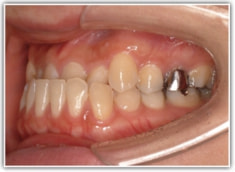

治療前